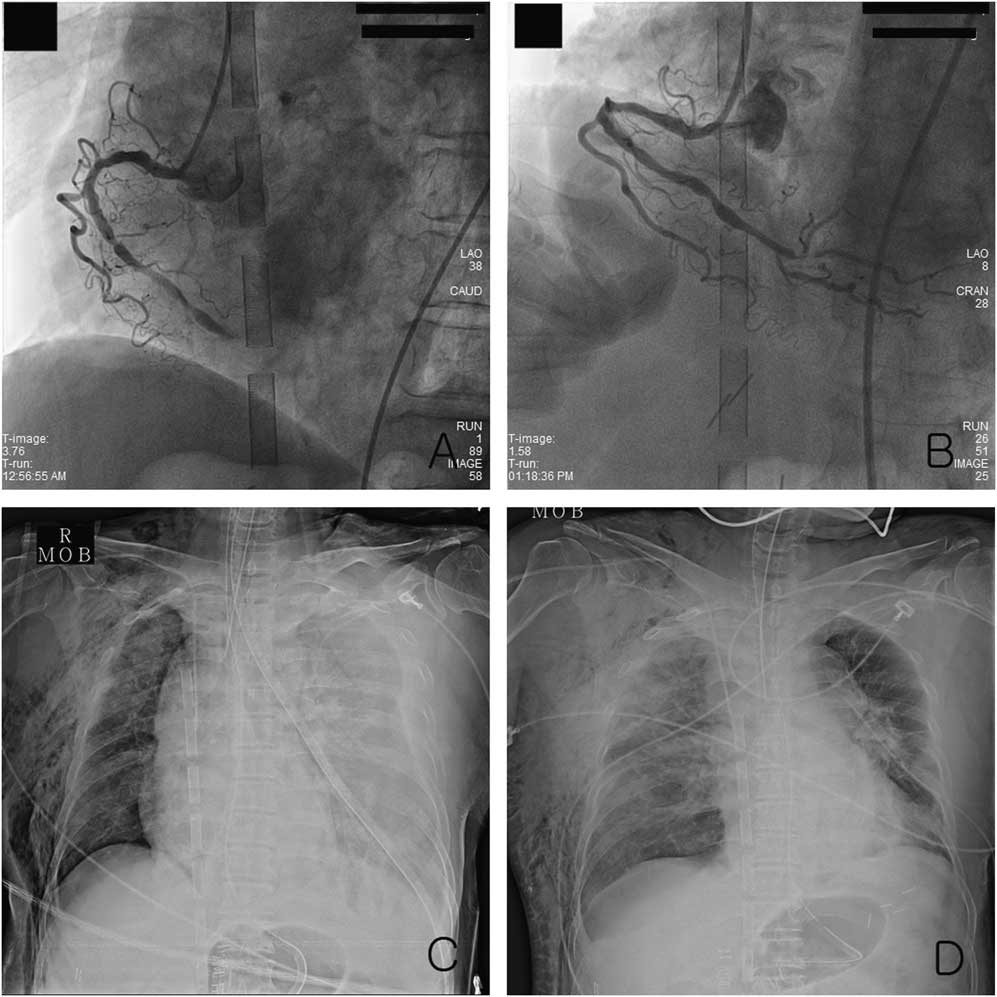

A 68-year-old woman with hypertension was admitted to the hospital for surgery to treat early-stage gastric cancer. The patient complained of diaphoresis while on the surgical ward on the morning of a planned discharge on the 8th postoperative day, and then experienced a cardiac arrest. Her initial rhythm was PEA, and this persisted despite advanced cardiac life support. The resuscitation team presumed the arrest to be of cardiac origin and activated the ECMO team. ECMO (Capiox Emergency Bypass System, Terumo Inc, Tokyo, Japan) was implemented during CPR at 51 minutes after arrest. After administration of inotropic agents and ECMO, the blood pressure was 70/40 mm Hg. Coronary angiography revealed total occlusion of the right coronary artery, and percutaneous coronary intervention (PCI) was performed (Figure 2, A and B). The following medications were administered: 300 mg aspirin, 600 mg clopidogrel, and 6000 IU heparin. Afterwards, echocardiography showed a small left ventricle with severe diffuse hypokinesia and ventricular systolic dysfunction. Despite maximal dosing of vasopressors, inotropic agents, and massive transfusion, hemodynamic instability persisted. Subcutaneous emphysema and pleural effusion were identified radiographically (see Figure 2, C). A left-sided tube thoracostomy was performed 3 hours after arrest, and 3660 mL of non-clotting blood drained over the next 6 hours. The patient underwent posterolateral thoracostomy 10 hours after arrest. A pericardial rupture near the pulmonary artery and a hematoma inside the thoracic cavity were observed. The patient showed refractory hemodynamic instability with a right-sided hemothorax on HD 2 (see Figure 2, D). Tube thoracostomy drained 780 mL of blood. The patient showed organ failure, coagulopathy, and refractory shock with severe ventricular dysfunction, despite ECMO, and died on HD 2.

Figure 2 The left anterior oblique view of coronary angiography: A) revealed total occlusion of the right coronary artery and B) improved arterial flow after percutaneous coronary intervention. Chest radiography showed C) a subcutaneous emphysema and left-sided pleural effusion before thoracotomy and D) a right-sided hemothorax and pulmonary edema on the 2nd hospital day after thoracotomy.